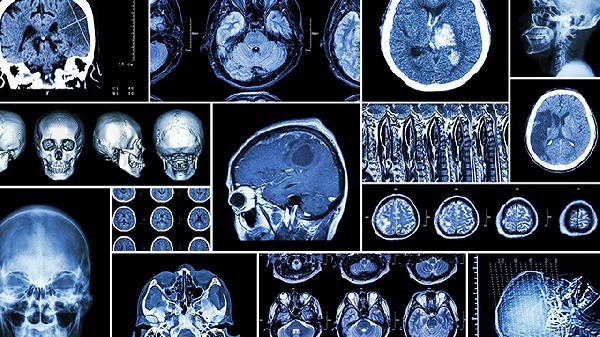

突发脑溢血

突发性脑溢血主要是好发于老年人的一种血管破裂性疾病,进而诱发压迫脑组织,引起脑组织发生水肿的一类疾病。